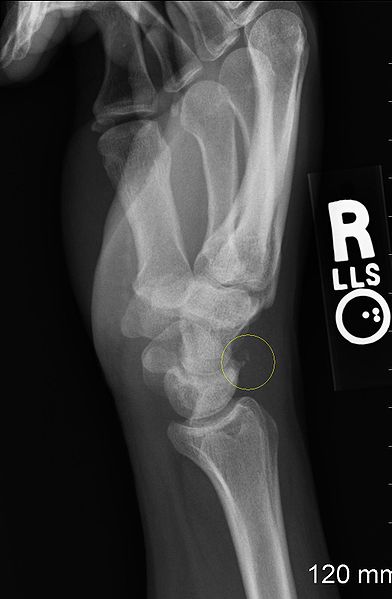

Following a bone fracture, the patient will first be managed/treated by a doctor, who will request for an X-ray before he or she decides on management option, be it conservative (no surgery) or surgery required.

The hand therapist often manages and treats fractures to hand, wrist and fingers.